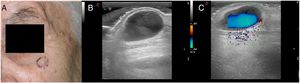

CASO 1: presentamos el caso de una mujer de 80 años con una pápula azulada de tiempo de evolución indeterminado, localizada en la mejilla izquierda (fig. 1). La lesión era asintomática. La ecografía mostró una lesión quística hipoecoica subdérmica con un Doppler color que demostraba un flujo turbulento (fig. 2). Se sospechó una ectasia venosa y se realizó una extirpación quirúrgica. El diagnóstico anatomopatológico final fue hidrocistoma.

CASO 2: el segundo caso fue un hombre de 72 años con un nódulo translúcido en la sien derecha (fig. 3). El diagnóstico clínico era sugestivo de un hidrocistoma. En la exploración ecográfica también observamos una lesión quística hipoecoica con un flujo turbulento en el Doppler color (fig. 4). El diagnóstico anatomopatológico final fue consistente con el diagnóstico clínico de hidrocistoma.